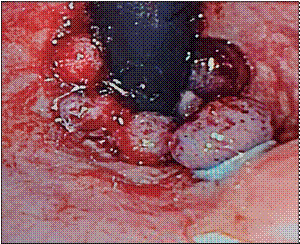

Se utilizaron endoscopios Olympus GIF-100 y Olympus GIF-Q-140, y sets de ligadura múltiple de Boston Scientific y Cook, los mismos que para ligadura de várices esofágicas. En retroflexión en recto, se identificaron las hemorroides (Fig. 1) y se realizó aspiración y colocación de bandas elásticas por lo menos 5 mm proximal a la línea pectínea (Fig. 2).

Figura 2. Ligadura de las hemorroides con cinco bandas elásticas.